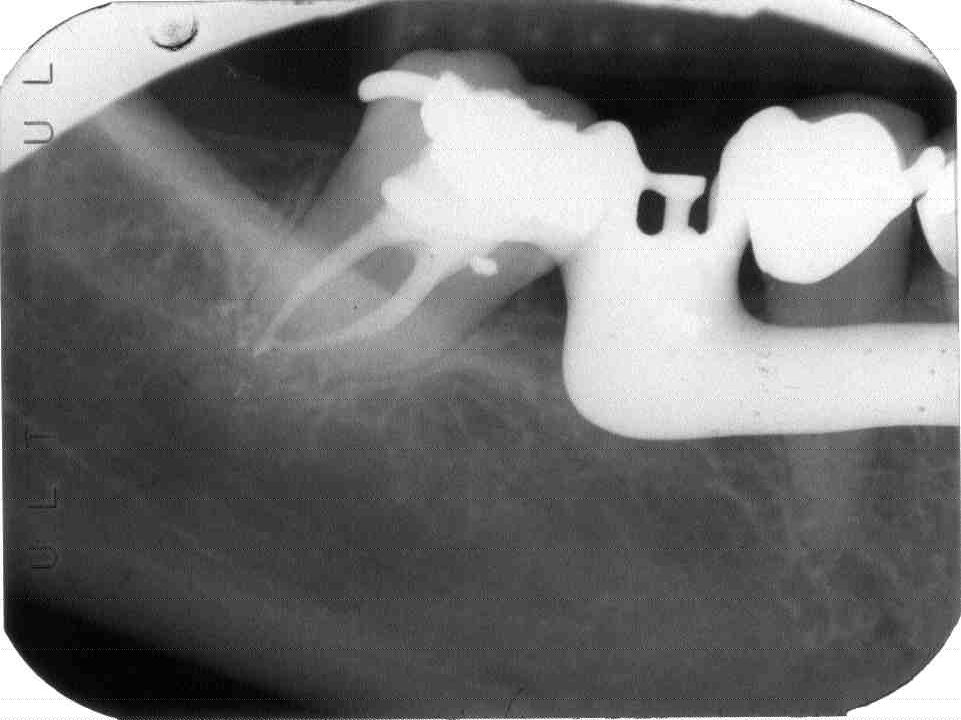

Background – Major Depressive Disorder (MDD/depression) is a mental illness characterized by marked sadness, and/or a loss of interest or pleasure in daily activities may be accompanied by weight loss, sleep disturbance, difficulty concentrating, and a high suicide rate. The disorder is very common in Canada with a lifetime prevalence rate of approximately 24%. Unfortunately, half of all patients with depression never see a physician and therefore go undiagnosed and untreated. Clinical Implications – Individuals under treatment for depression and those whose illness has not been diagnosed often present to the dentist with significant oral disease. Dentists need to be cognizant of how to safely and compassionately provide care to those already receiving mental health services. They must also be familiar with the psychiatric symptoms of the disorder so that they can effectuate a timely referral to a physician of those with occult or relapsing disease. Depression is frequently associated with a disinterest in performing oral hygiene, a cariogenic diet, rampant dental decay, advanced periodontal disease, and oral dysesthesias. Antidepressants used to treat the disease cause the xerostomia and may increase the severity of dental disease. Appropriate dental management necessitates a vigorous preventive dental education program, the use of artificial salivary products, antiseptic mouthwash, daily fluoride mouth rinse, and special precautions when administering local anesthetics with vasoconstrictors and prescribing analgesics. Conclusions — Dentists invoking appropriate precautions can usually provide a full range of services to individuals with major depressive disorder thereby enhancing patient self esteem and contributing to the therapeutic milieu.